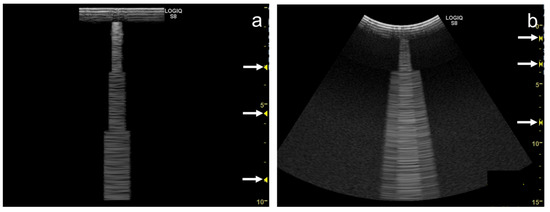

3.3. Frequency